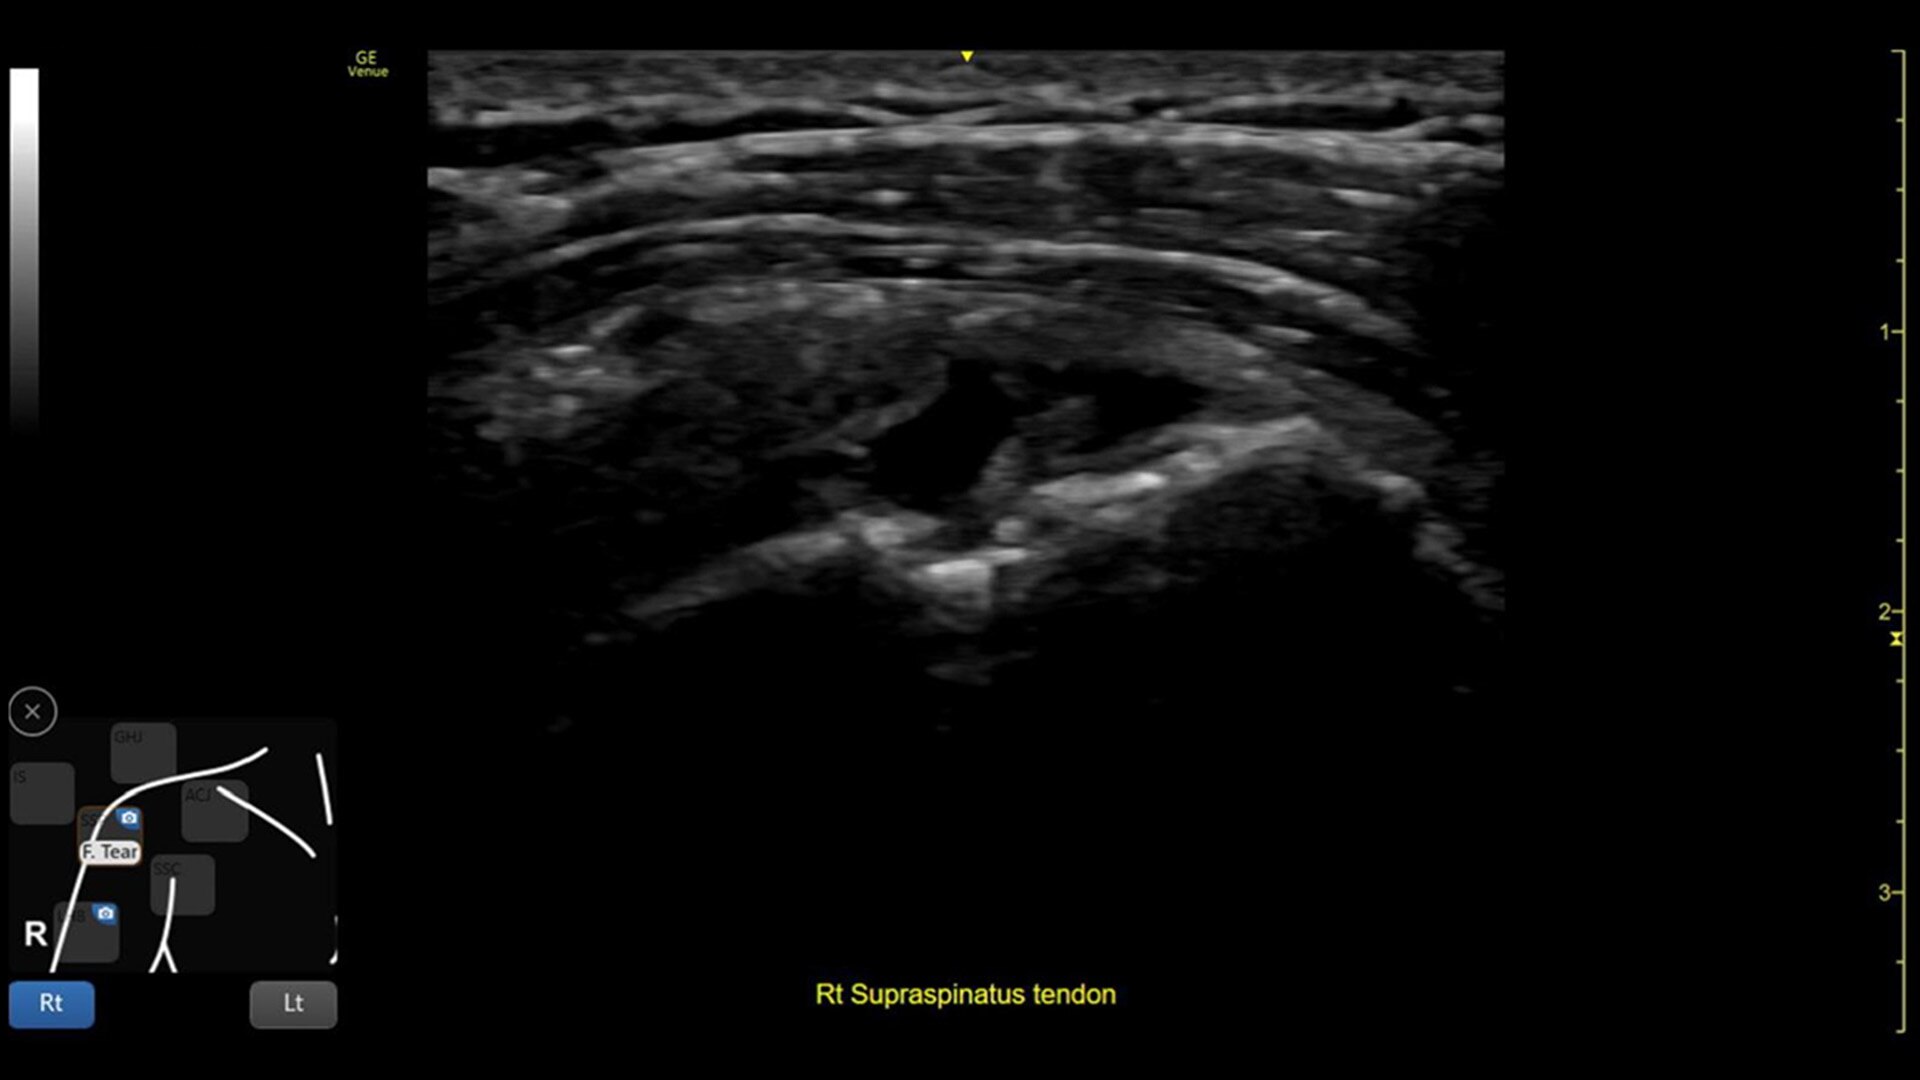

Venue Coach MSK

Simplifying MSK scans

This easy-to-use exam documentation tool assists users through exams by providing reference images and anatomy markups. Multiple anatomical areas and helpful video tutorials help clinicians to acquire the scans they need.

MSK Diagrams: Simplifies documentation and assists the clinician in follow up for patients. No need to manually type findings—you can simply assign a label from a pre-populated list that correlates with the images. Get a single view diagram with one click image storing, keep track of assessments and show trends in response to therapy.

Reference Image: Reference image provides anatomy mark-ups to assist novice users in scanning the correct anatomy